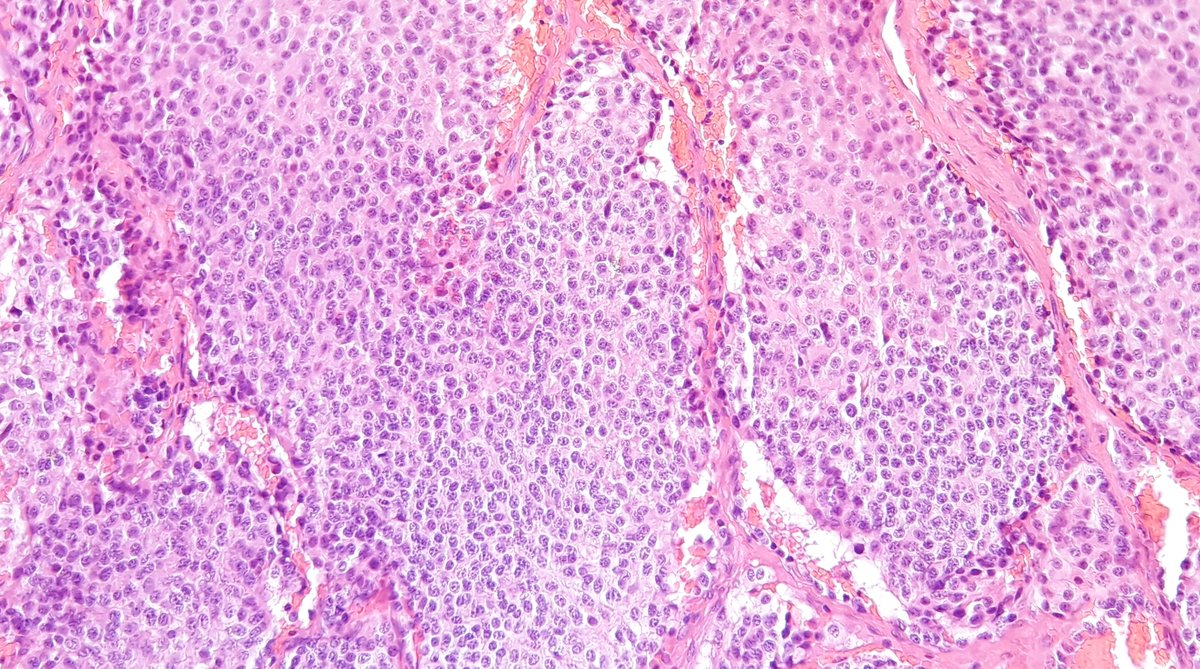

Here a unusual thymic tumor : atypical carcinoid !

#pathology#thymus#pulmpath Organoid clusters of cells with round nuclei and fine chromatin. Synapto+. Atypical carcinoid because more than 2 mitoses/mm2 and some foci of necrosis. pic.twitter.com/xHIsZDQgBj